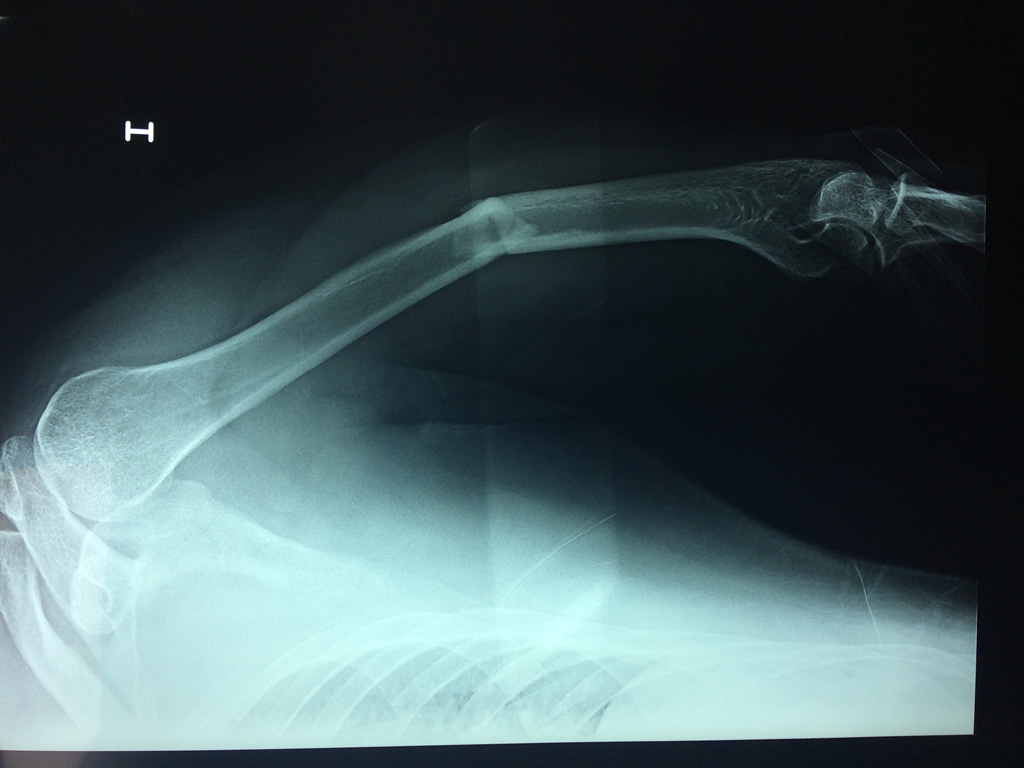

Cirugías de Húmero - Húmero

El Húmero (en latín, humerus) es el hueso más largo de las extremidades superiores en el ser humano. Forma parte del esqueleto apendicular superior y está ubicado en la región del brazo. ... El extremo proximal del húmero tiene la cabeza, cuellos quirúrgico y anatómico y tubérculos mayor y menor.